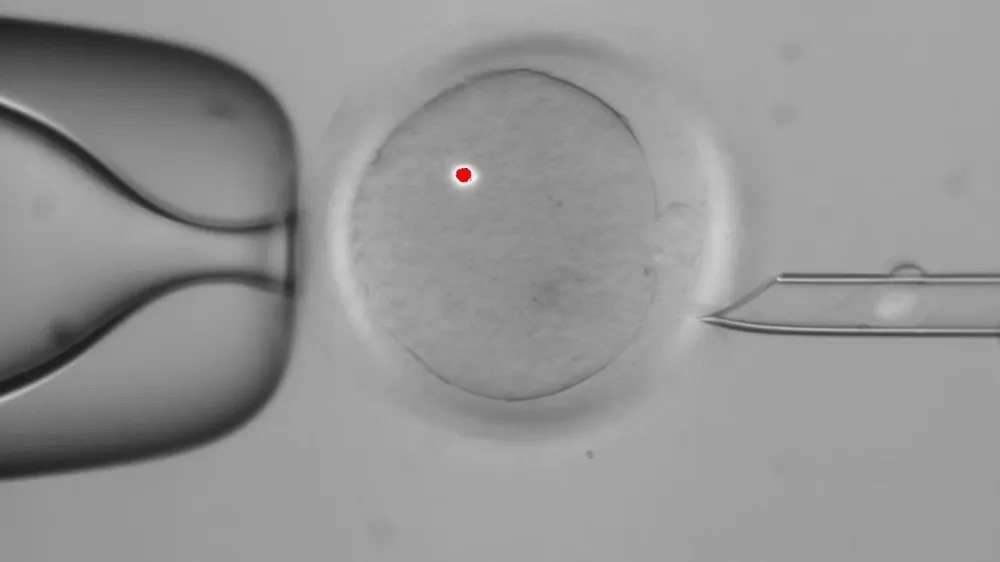

Científicos en Oregón han creado embriones con genes de un hombre y dos mujeres usando una técnica audaz que algún día podría usarse para impedir que los bebés hereden ciertas enfermedades incurables.

Según publicó la semana pasada la revista Nature, los expertos consiguieron sustituir el ADN mitocondrial defectuoso por el genoma mitocondrial libre de mutaciones dañinas de una donante y obtuvieron así un óvulo capaz de producir con normalidad blastocitos (embriones de hasta cinco días de vida) y células madre embrionarias.

El bebé que naciese de este óvulo tendría todos los rasgos genéticos de su madre biológica pero portaría el genoma mitocondrial de la donante y estaría libre de las enfermedades que, de otro modo, le hubiese transmitido su progenitora, según explicó el investigador Shoukhrat Mitalipov en una rueda de prensa.